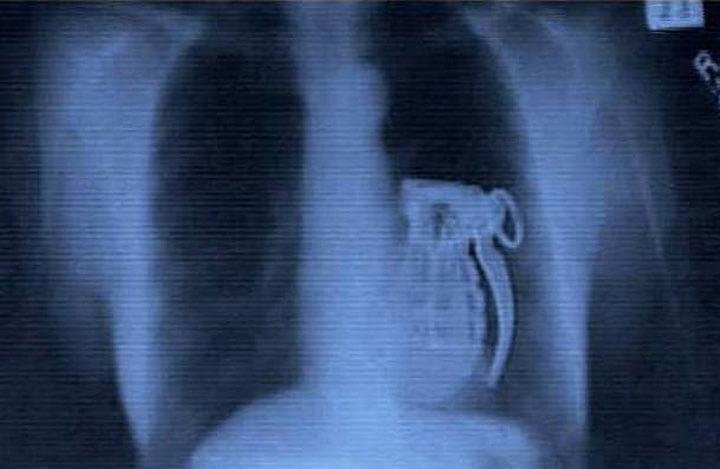

7. Врачи обнаружили это в животе у cмepтника. По своей глупости он просто забыл вытащить чеку